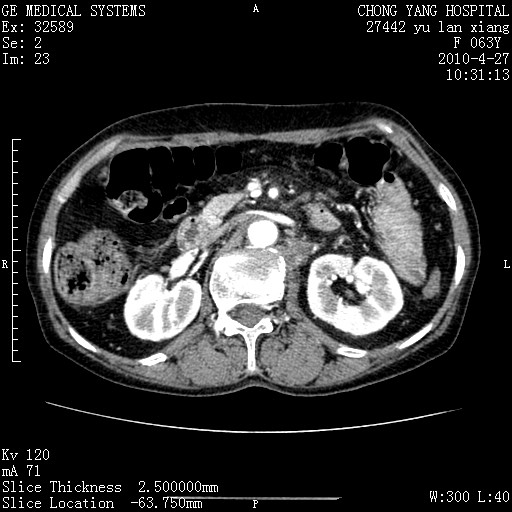

标题: CT26066:F63Y 上腹正中压痛半月,CA199:7400u/ml,MR示胰腺炎伴 [打印本页]

胰腺癌侵犯腹腔动脉干-分支、胃壁、左侧膈肌伴胰周及腹膜后淋巴结转移、胆囊切除术后。

胰腺癌侵犯腹腔动脉干-分支、胃壁、左侧膈肌伴胰周及腹膜后淋巴结转移、胆囊未显影。